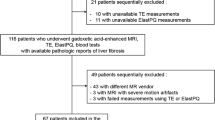

The institutional review board approved this prospective study, and all study participants provided written informed consent prior to MRI examination. From June 2019 to March 2020, patients with AIH diagnosis were consequently included in this study. Diagnosis of AIH was based on diagnostic criteria of AIH, established by the International Autoimmune Hepatitis Group (IAIHG) [24]. Also patients with overlap syndromes, which implies that the predominant disease is AIH and that the concurrent cholestatic features are background components [25], were included.